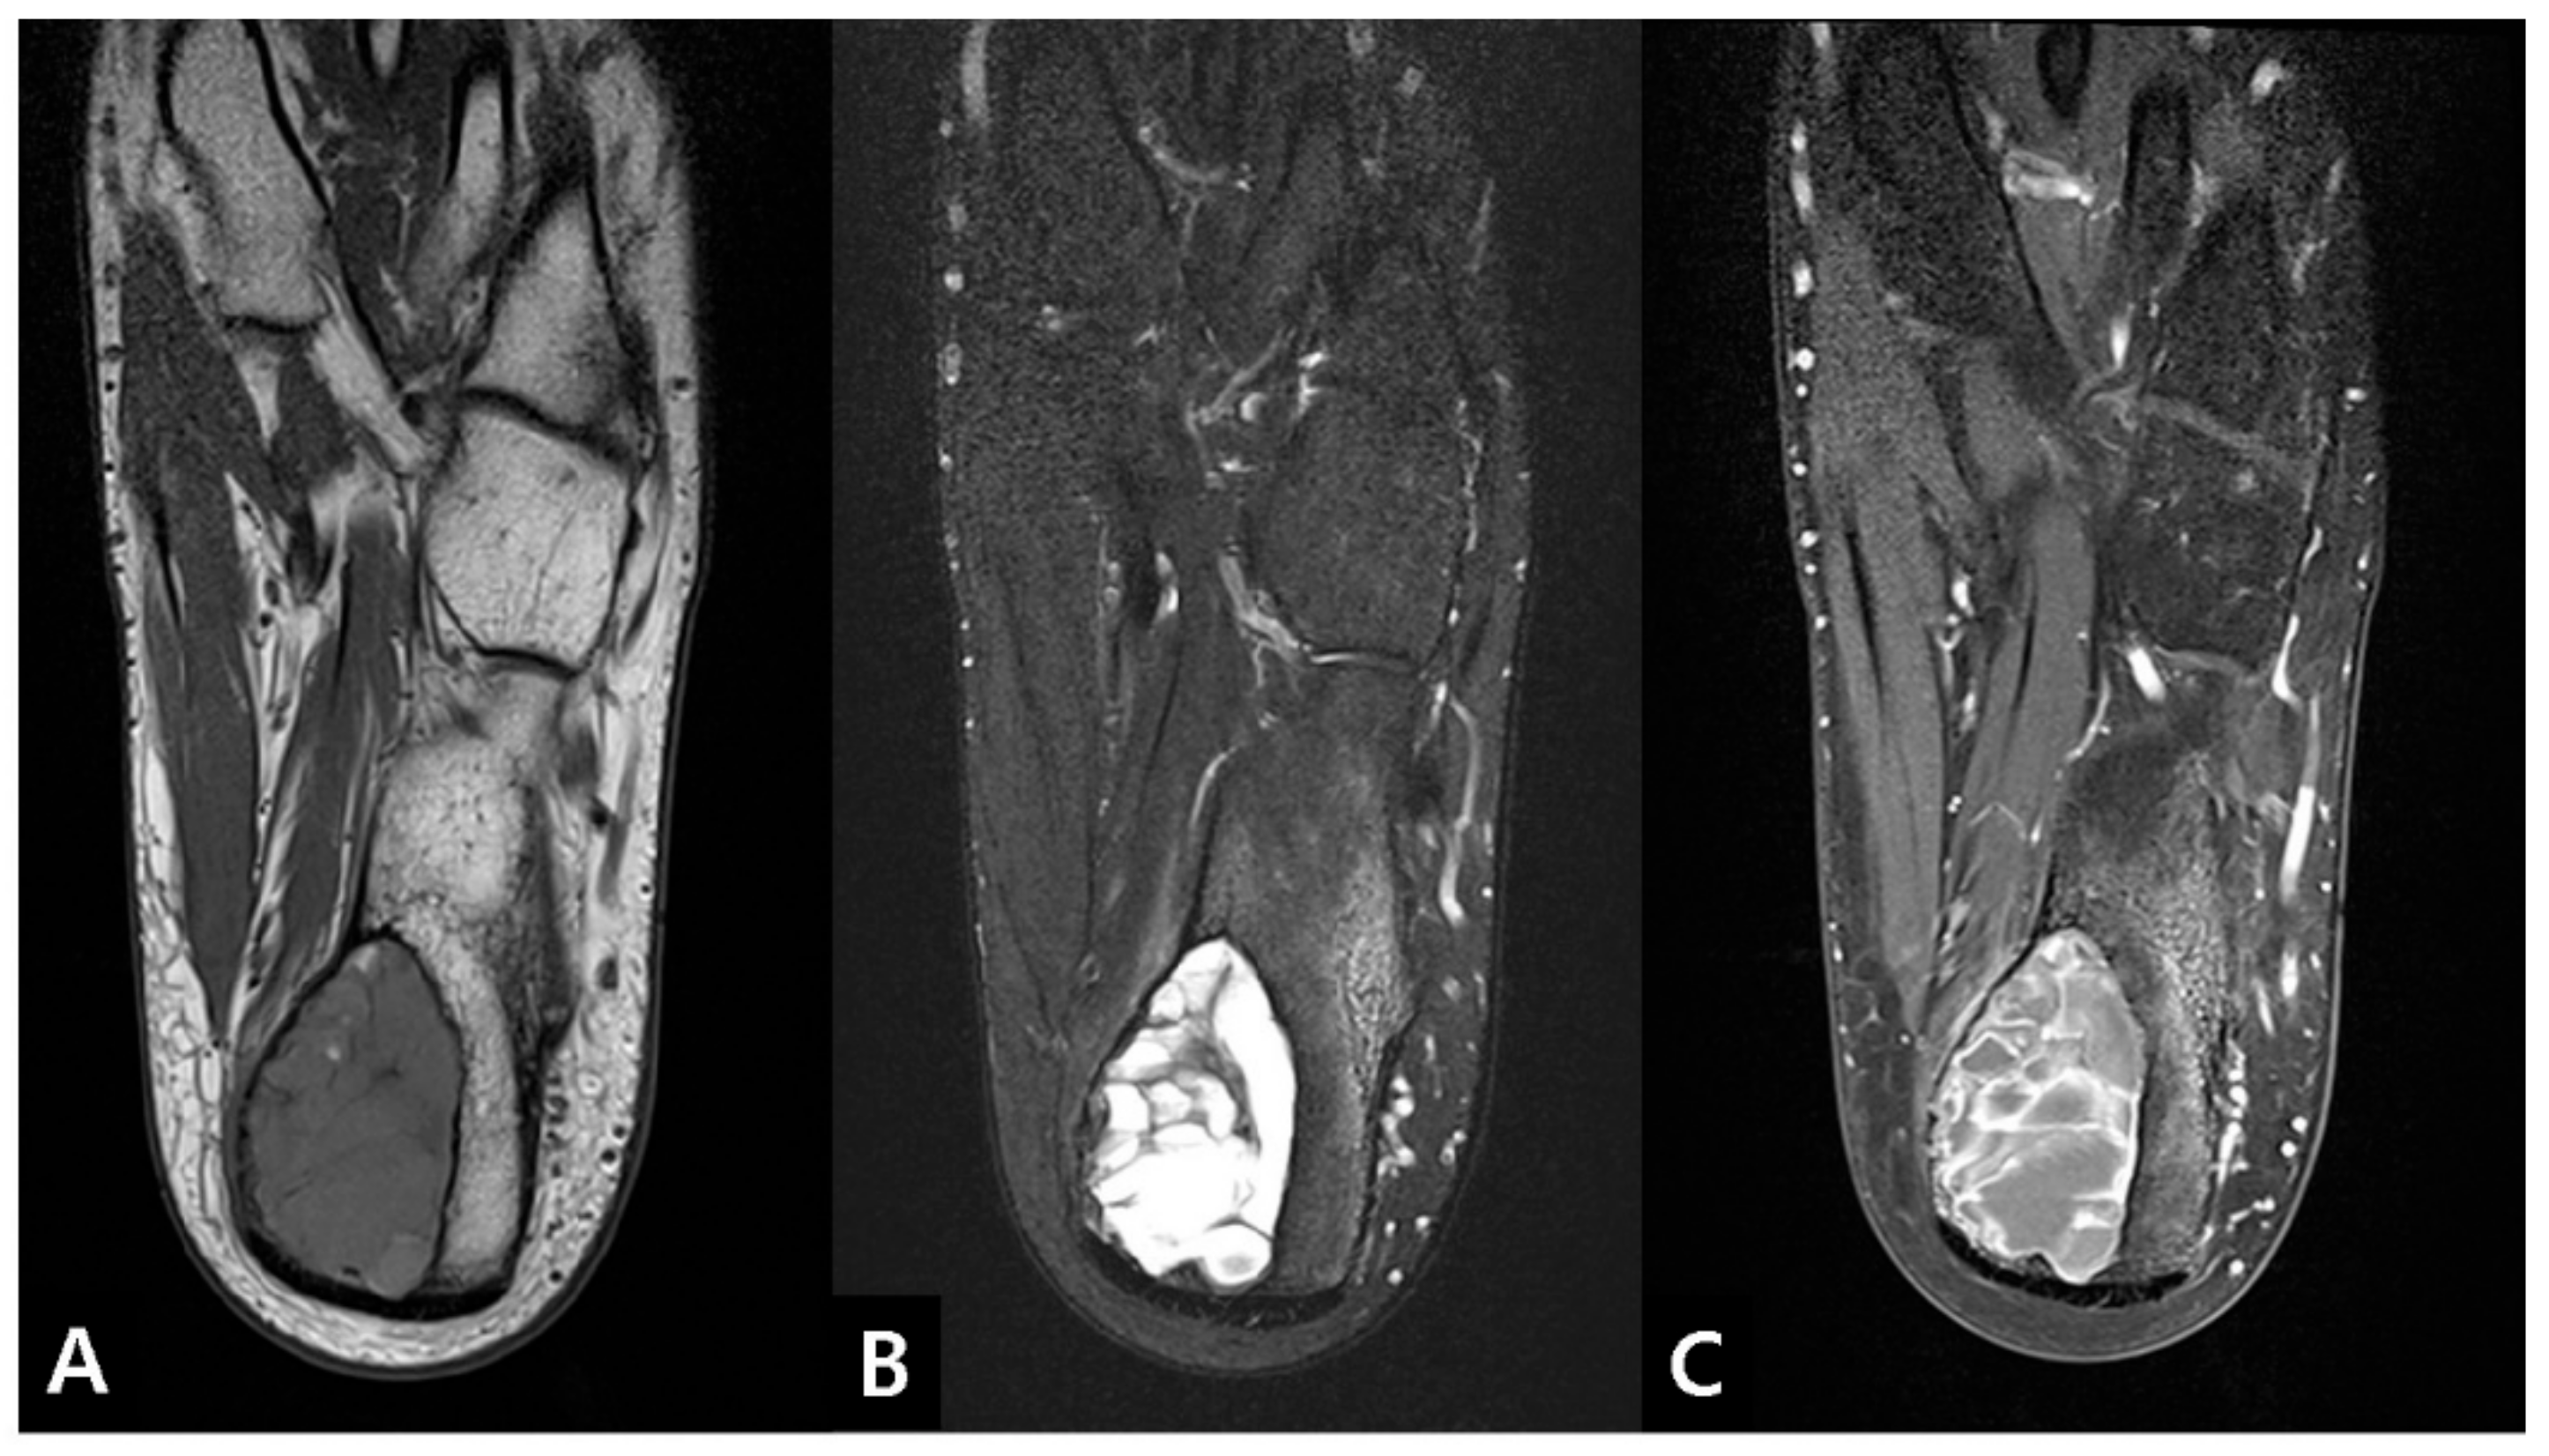

2. Case Presentation

2.1. Preoperative Evaluation